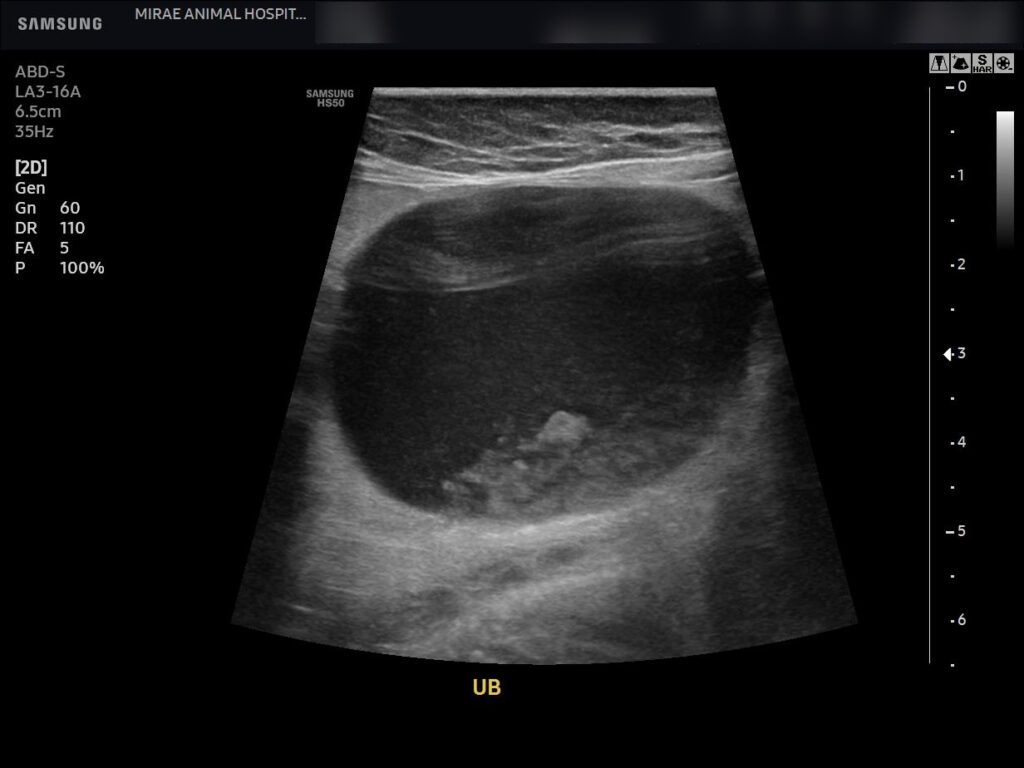

이어 시행한 복부 초음파 검사에서는 방광 내부에 다량의 슬러지가 관찰되었고, 슬러지가 방광 내에 넓게 분포된 상태였습니다.

방광 팽대 역시 매우 뚜렷하게 확인되었습니다. 다행히 양측 신장은 수신증 소견 없이 형태와 구조가 양호한 상태로 평가되었습니다.

환자의 복부 초음파 검사 / 출처: 미래동물의료센터